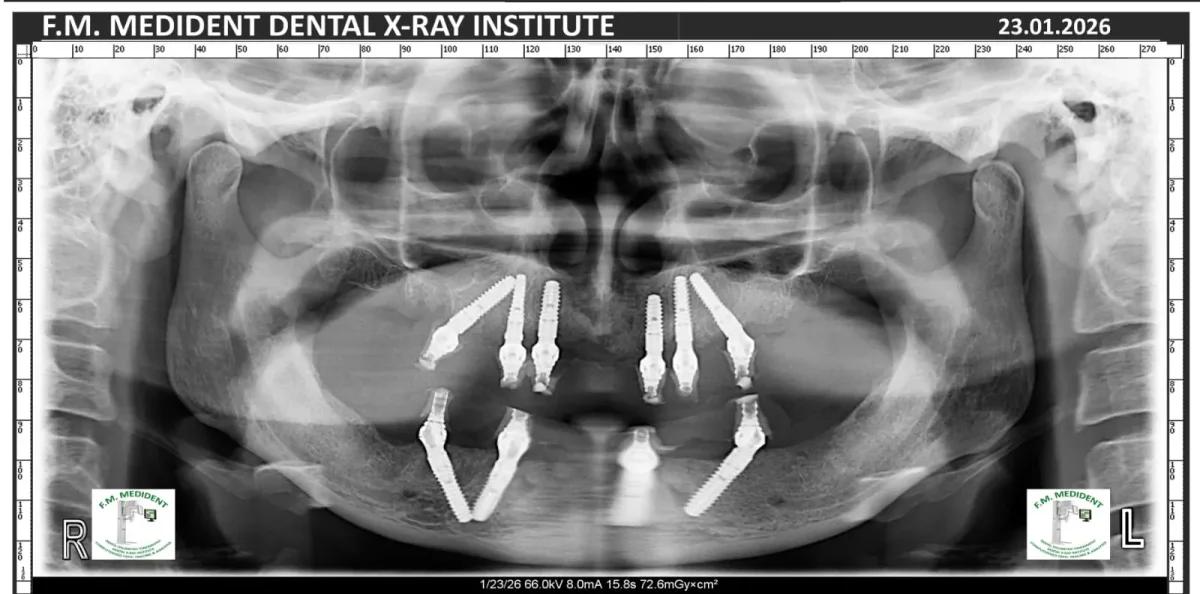

Cazuri reale înainte și după, din tratamente realizate în clinică.

Înainte

DupăExemple reale din cazuri tratate în clinică.